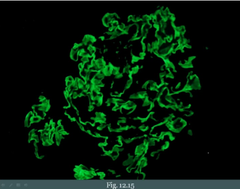

Ovarian Tumor Overview

Surface epithelium (coelomic) - 70% (most common) - Types: serous/mucus cystadenoma/adenocarcinoma; endometrioid (from ovarian endometriosis); brenner (bladder-like) - Symptoms: vague pain, urinary compression - Can cause omental caking - CA-125 tumor-marker Germ Cell Tumors (from the egg) - 15% (2nd most common) - Mimics tissue subtype - Types: fetal (cystic teratoma, embryonal carcinoma); oocytes (dysgerminoma); yolk sac (endodermal sinus); placenta (choricocarcinoma) Sex-Cord Stroma (from CT - fibroblasts, granulosa, theca) - Types: granulosa-theca, sertoli-leydig, fibroma Metastasis - Kruckenberg (bilateral mucinous, signet ring cells, from GI/gastric) - Pseudomyxoma peritonei (mucus in peritoneum, due to appendix or ovary tumor)